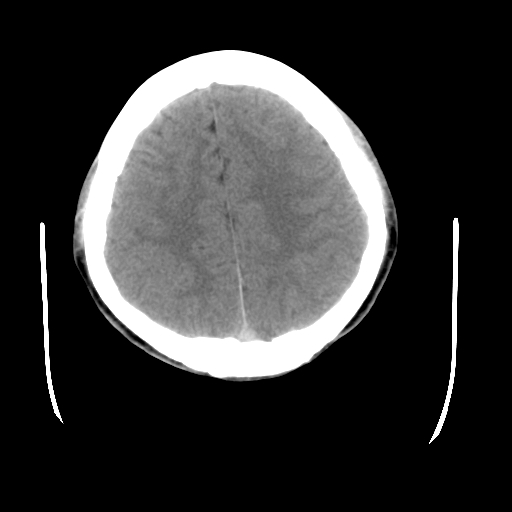

标题: CT23601:男, 17岁,剧烈头痛一小时。 [打印本页]

标题: CT23601:男, 17岁,剧烈头痛一小时。

男, 17岁,剧烈头痛一小时。

颅脑ct轴位平扫颅内未见明确异常;建议:必要时复查。

颅脑ct轴位平扫颅内未见异常。建议短期复查。